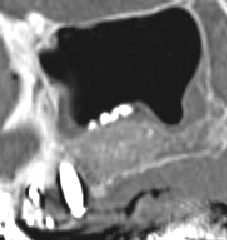

Photos extraites de la vidéo :

1 mois pot-op